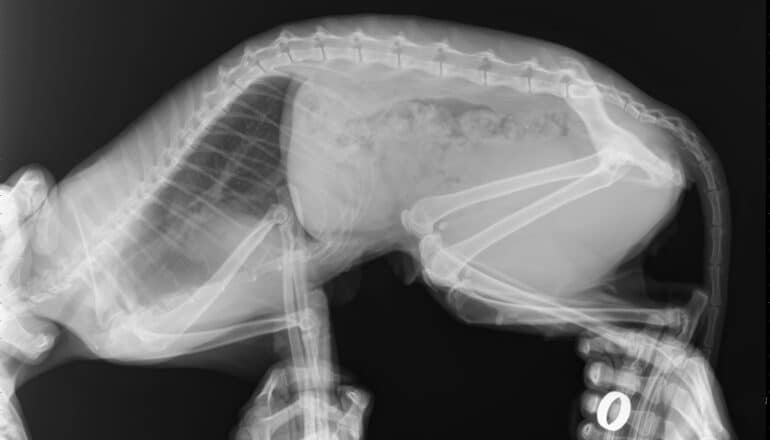

x-ray image of cat abdomen